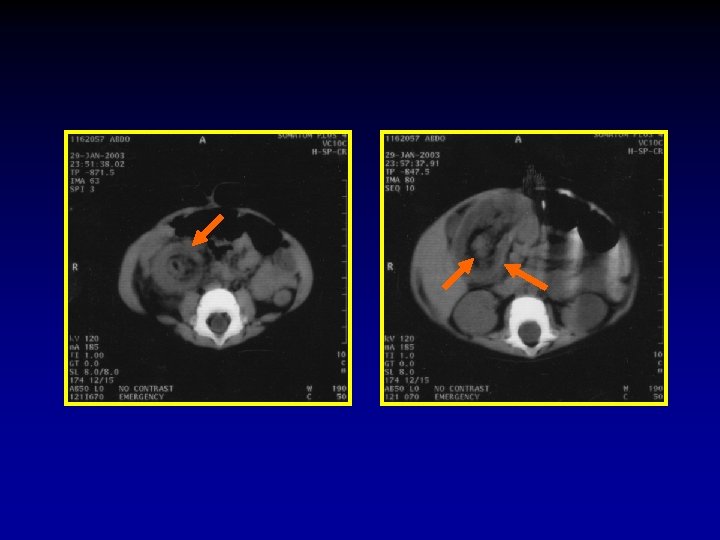

6. Are there signs of threatened bowel wall viability or not? The CT signs of threatened bowel wall viability: 1) Thickening of the bowel wall with or without the target sign. 2) Pneumatosis (Air in the bowel wall). 3) Portal venous gas. 4) Increased density of the bowel wall without intravenous contrast administration. 5) Mesenteric haziness, fluid, or hemorrhage often associated with generalized ascites. 6) On intravenous contrast enhanced CT, non enhancement, or rarely increased enhancement of the bowel.

Thickening of. Pneumatosis Engorgement the bowel Mesenteric Associated wall (Air of with Mesenteric in. Haziness Ascites the or bowel without Vessels wall) the target sign